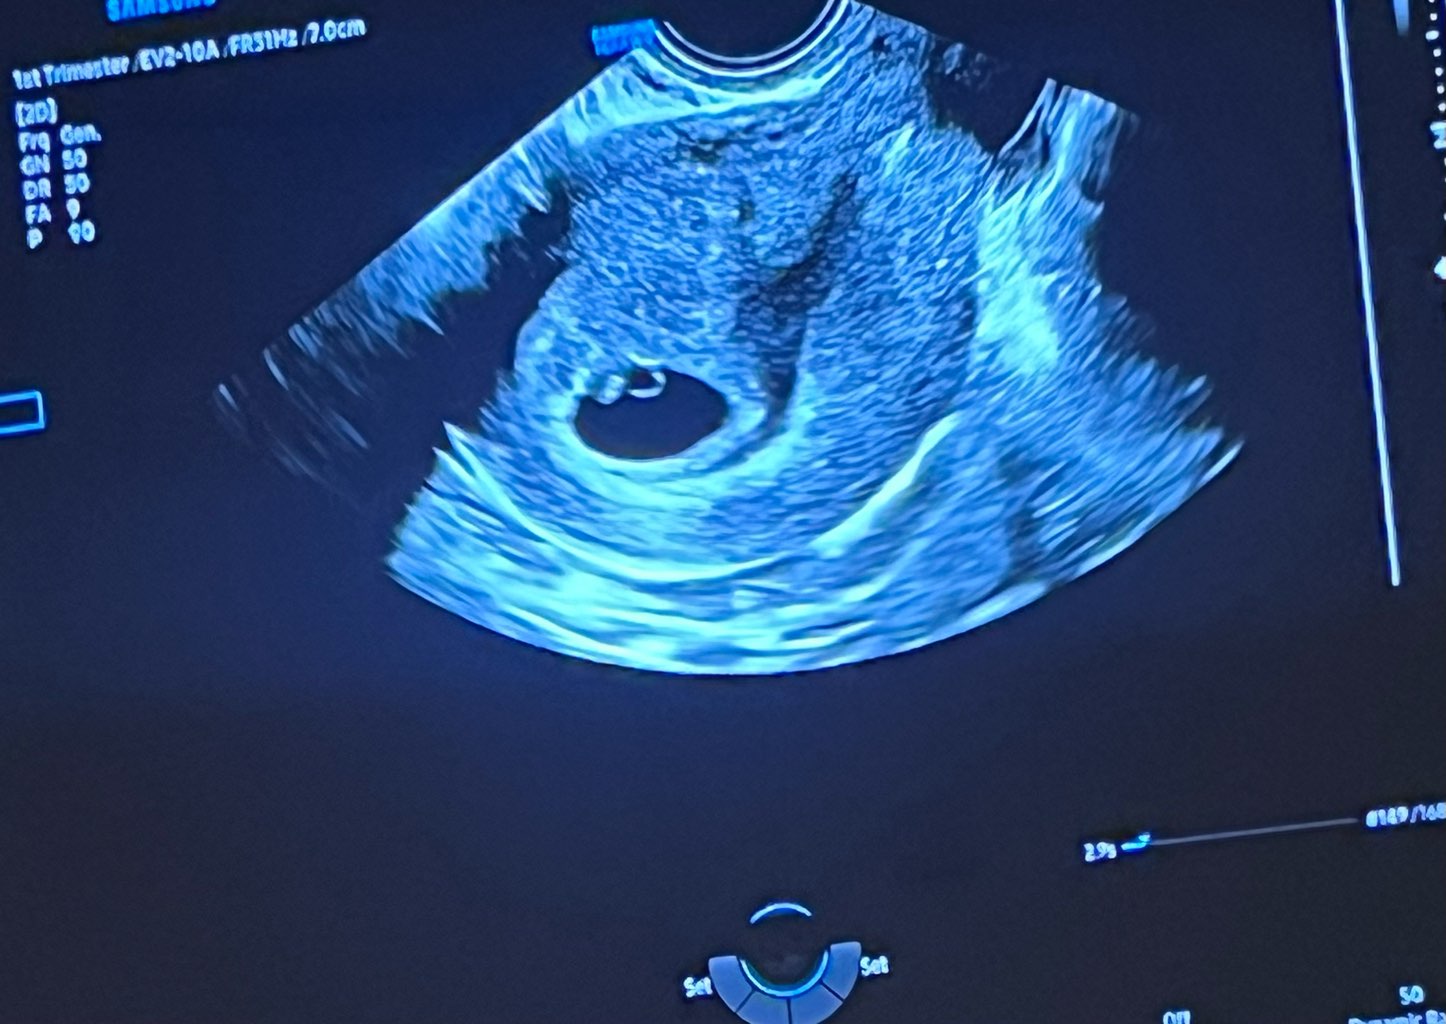

Ja się melduję że mamy serduszko ❤️

Załączniki

• IMG_4639.jpeg

IMG_4639.jpeg

177,8 KB · Wyświetleń: 118